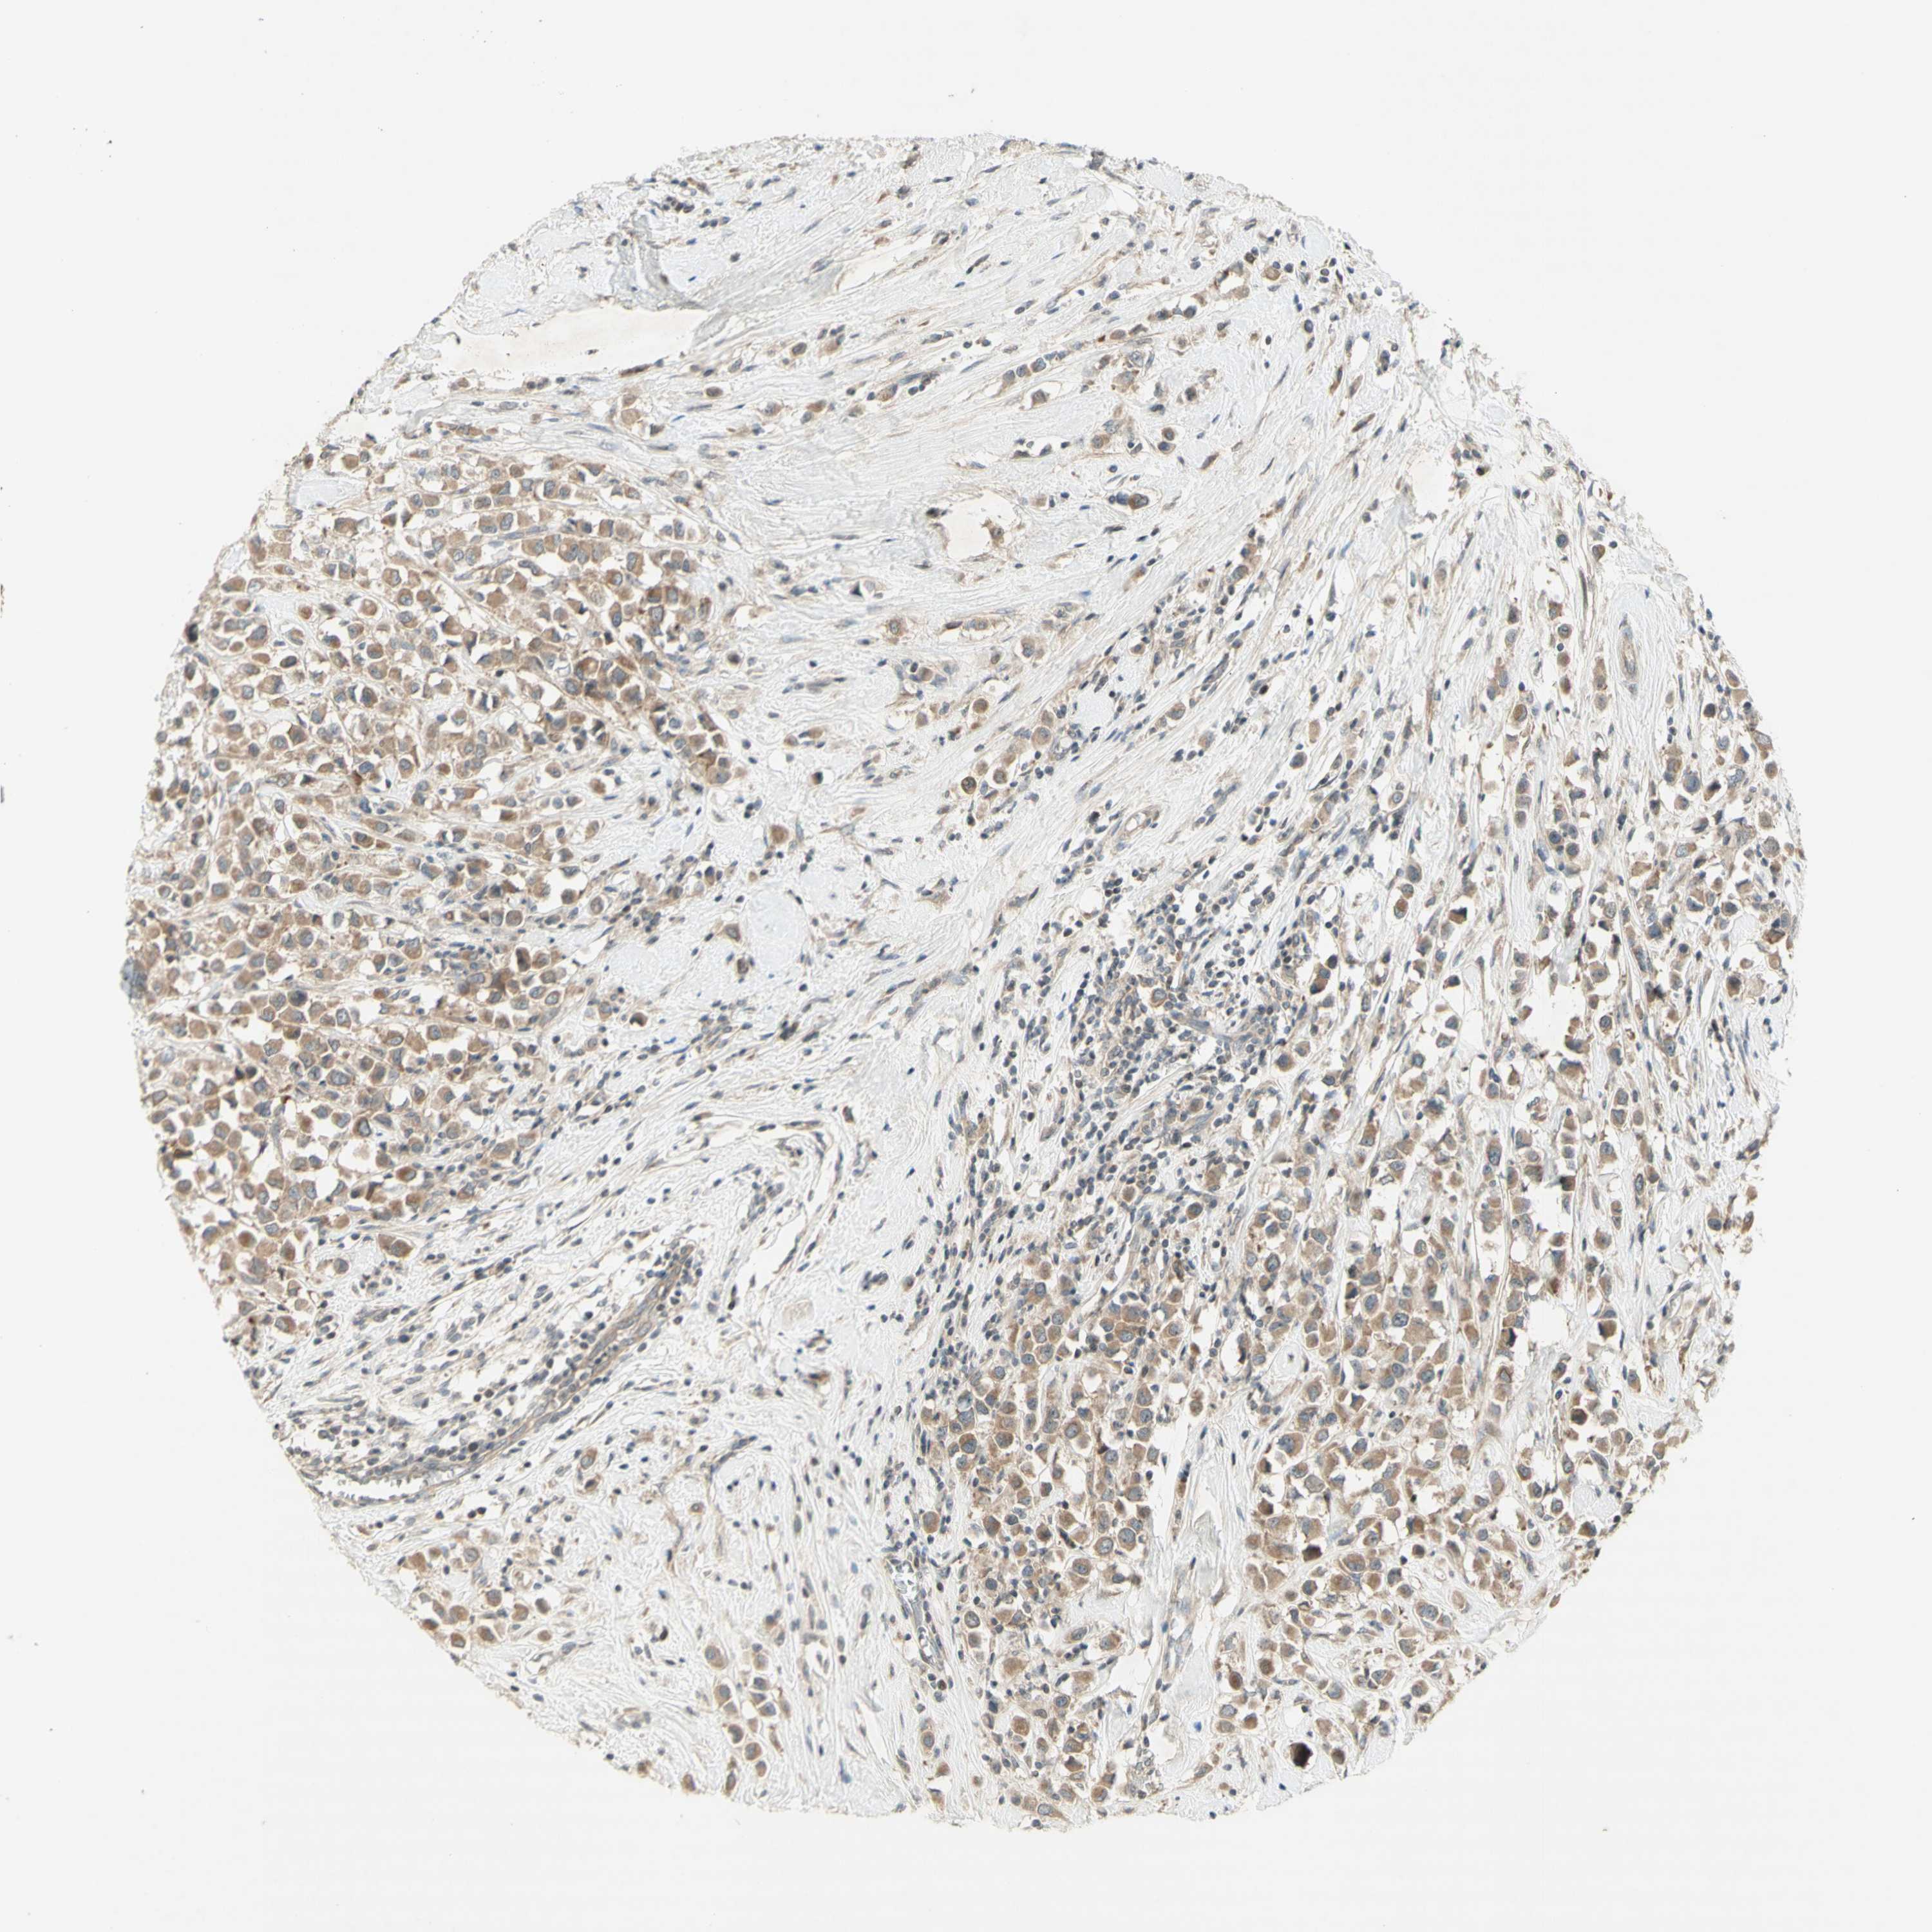

BRCA TCGA BRCA VALIDATION PROTEIN EXPRESSION